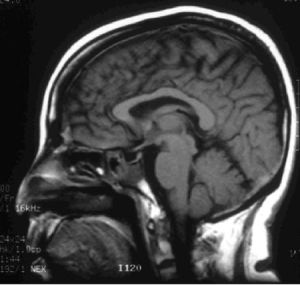

(1)蝶鞍像為基本檢查之一。在垂體瘤很小時蝶鞍可以沒有變化,由於腫瘤日漸長大,可致蝶鞍擴大、骨質破壞,鞍背侵襲等。(2)CT檢查採用靜脈注射造影劑增強後,可顯示出5mm大小的垂體腺瘤。更小的腫瘤顯示仍有困難。